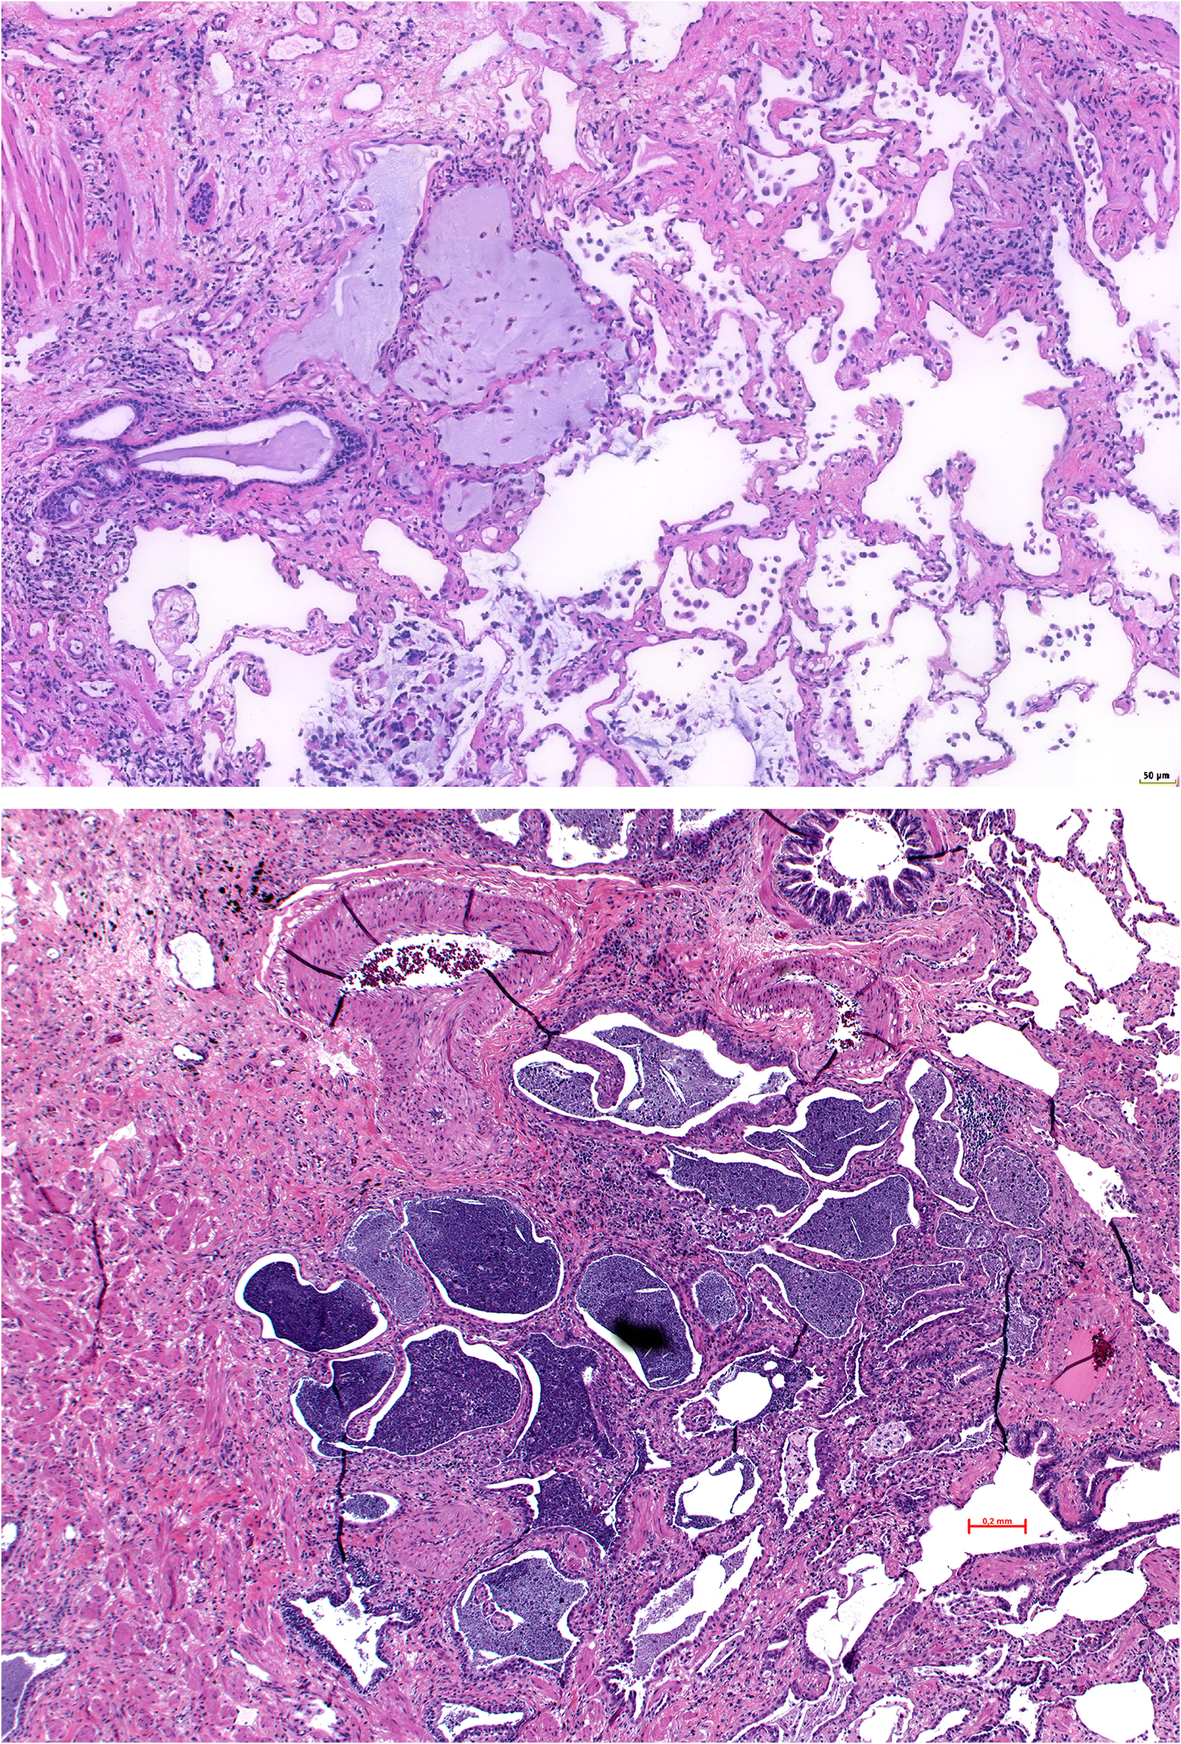

Fig. 5

Mucostasis, in the cystic structures in UIP; in the upper panel there is mucus accumulation with a few scattered macrophages; in the lower panel there is dense spissated mucus, macrophages and scattered neutrophils; this usually is a sign of bacterial colonization. There are also aggregates of lymphocytes around the cysts, which later on can progress into lymph follicles. H&E, bars 50 and 200 μm